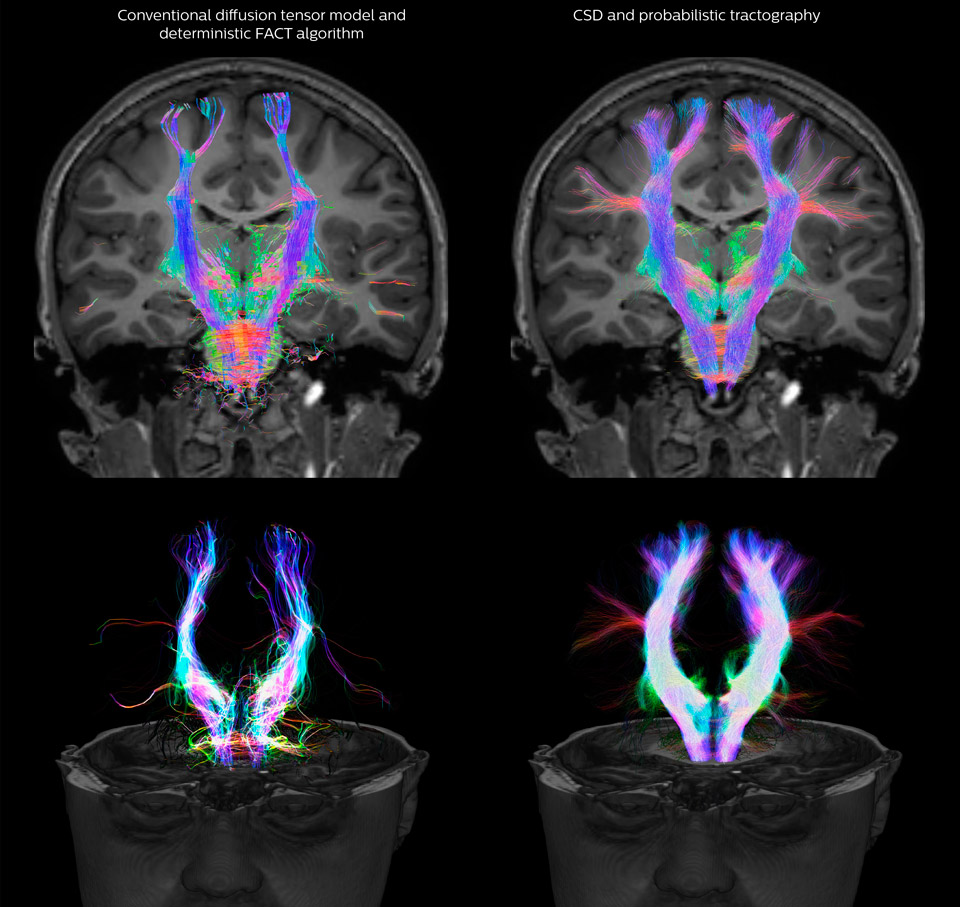

Fiber tractography of the corticospinal tract with seed region of the posterior limb of the internal capsule. Different processing based on the same data.

All images were created from the same acquisition in a child using Ingenia 3.0T CX and 32-channel dS Head coil. Diffusion data was acquired at b-values 0, 500, 1000, 2000, 3000. The use of high b-values (3000 s/mm2) effectively suppresses extra-axonal water signal and provides high angular resolution.

Data processing was performed using open source software. Fiber tracking was performed using the MRtrix package (J-D Tournier, Brain Research Institute, Melbourne, Australia, https://github.com/MRtrix3/mrtrix3), Tournier et al. 2012. DEC TDI based on F Calamante et al 2010.

CSD of multishell DWI results in the white matter FOD at each voxel. Unlike the conventional diffusion tensor model, this approach enables accurate modeling of multiple fiber populations within a single voxel.